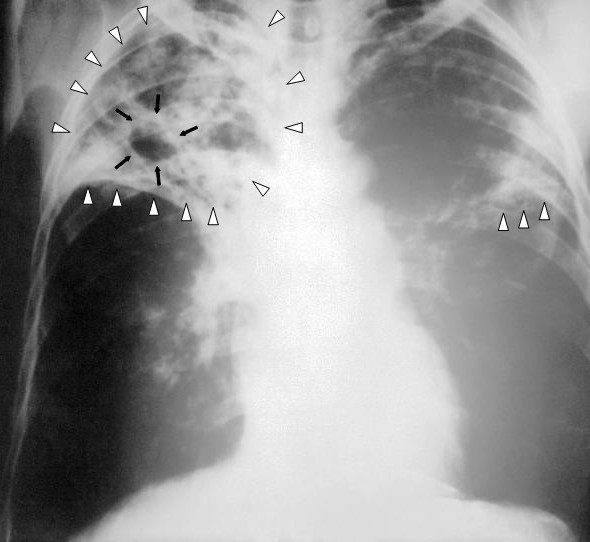

| 結核患者の胸をX線撮影した写真 | |